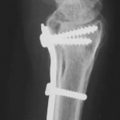

Rigid stable fixation of the osteotomy site is essential for predictable union, early postoperative mobilization, and optimal outcomes

2.0/2.4 mm metal plates and screws are typically used to achieve stable fixation of metacarpal osteotomy sites

Many plating systems include purpose-made corrective osteotomy plates with oblong holes that facilitate angular stability, while permitting rotational adjustment, which allows the surgeon to “dial in” the degree of correction desired

The use of locking screws minimizes undesired deformation of osteosynthesis site during fixation